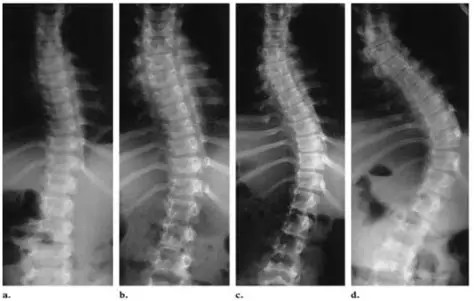

Schroth yöntemi, skolyozda omurgayı üç boyutlu olarak ele alan, kişiye özel planlanan bir egzersiz ve postür eğitim yaklaşımıdır. Amaç; omurgadaki eğrilik, rotasyon ve duruş bozukluklarını kontrol altına almak ve kişinin günlük yaşamda doğru postürü öğrenmesini sağlamaktır.